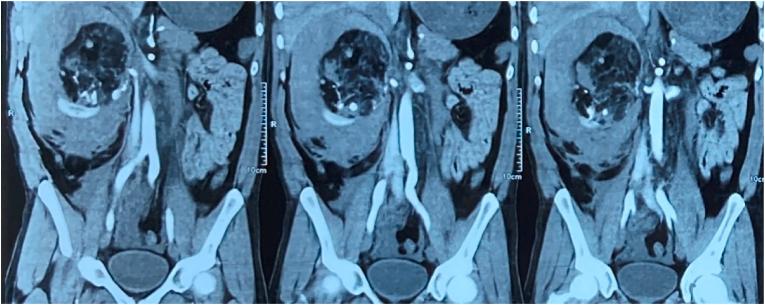

CT scan showed renal angiomyolipoma with aneurysm formation and bleed from the lesion. Blood profile revealed low hemoglobin.

C 临床发现与检查:CT扫描显示肾血管平滑肌脂肪瘤伴有动脉瘤形成及病变出血。血常规显示血红蛋白降低。